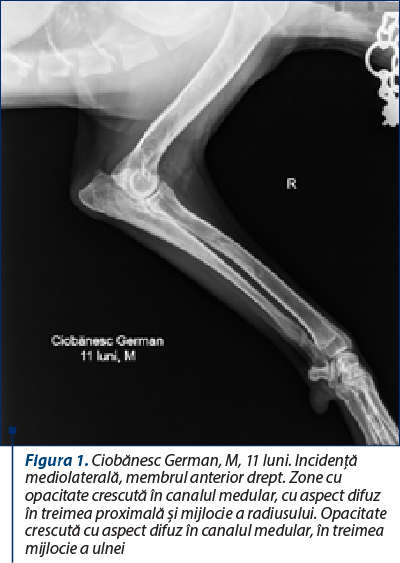

Modificările radiografice se prezintă într-o gamă variată de semne, în funcţie de momentul evolutiv al bolii. Boala prezintă trei faze (una precoce, una mijlocie şi una tardivă), din care prima fază este greu de surprins radiografic (Pollard şi Phillips, 2018; Kieves, 2021). Deşi poate afecta orice parte a diafizei unui os lung, de cele mai multe ori procesul debutează în apropierea orificiului arterei nutritive diafizare. Semnul iniţial este reprezentat de o scădere a opacităţii canalului medular în jurul orificiului arterei nutritive a osului (faza 1). Apoi, se produce o creştere focală a opacităţii endostului, rezultând zone bine delimitate în canalul medular, cu opacitate similară corticalei diafizare. Pe măsură ce boala evoluează, leziunile osoase progresează, focarele cu opacitate crescută fuzionează, transformându-se în focare cu aspect neuniform, difuz, cu tendinţă de extindere pe o zonă cât mai mare din canalul medular diafizar (faza a doua) (figurile 1 şi 2). Periostul din apropierea zonelor afectate poate deveni evident, constatându-se o reacţie periostală omogenă, fenomen observat la 15-50% din cazuri (Trostel şi col., 2003; Kieves, 2021). Ulterior, se constată că zonele din canalul medular îşi diminuează opacitatea şi dispar, astfel că, din punct de vedere radiografic, osul îşi recapătă aspectul iniţial (faza a treia) (Tudor şi Vlăgioiu, 2015). Examenul radiografic este necesar atât pentru confirmarea diagnosticului, cât şi pentru excluderea altor afecţiuni osteoarticulare. Diagnosticul diferenţial se face cu alte osteopatii ale tineretului, caracterizate prin şchiopătură şi sensibilitate osoasă, cum ar fi osteodistrofia hipertrofică, hiperparatiroidismul secundar nutriţional, rahitismul, osteomielita etc.

Figura 1. Ciobănesc German, M, 11 luni. Incidenţă mediolaterală, membrul anterior drept. Zone cu opacitate crescută în canalul medular, cu aspect difuz în treimea proximală şi mijlocie a radiusului. Opacitate crescută cu aspect difuz în canalul medular, în treimea mijlocie a ulnei